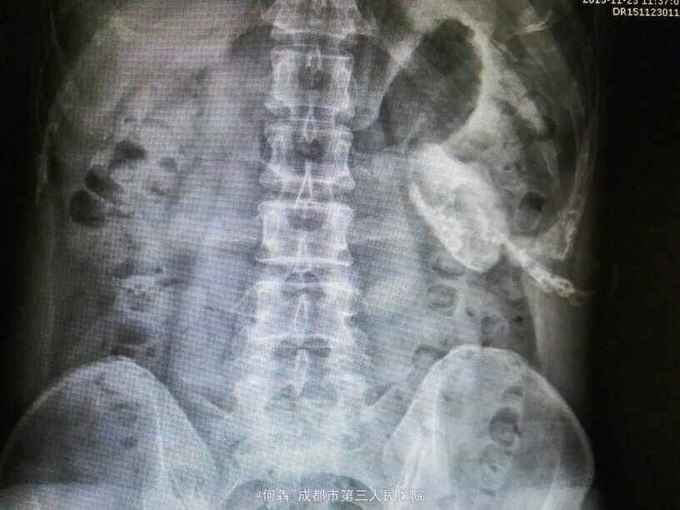

53岁,男性,因“腹腔镜下双肾囊肿切除术后1年余,左腰部窦道形成10月余”入院。无高血压病及糖尿病。

左腰部窦道形成伴少许脓液。窦道脓液培养出绿脓杆菌。

腹腔镜双肾囊肿切除术后窦道形成伴感染。现使用敏感抗生素派拉西林舒巴坦抗感染。